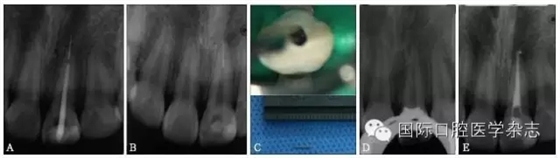

超聲技術(shù)作為經(jīng)典且有效地取出分離器械的方法之一,具有獨(dú)到的優(yōu)勢(shì)。超聲工作尖可以在顯微鏡直視下在根管內(nèi)運(yùn)動(dòng),且能夠不對(duì)稱(chēng)地去除分離器械周?chē)难辣举|(zhì),若只在分離器械一側(cè)局部運(yùn)動(dòng)即能取出分離器械,則有利于保存根管壁較薄一側(cè)的牙本質(zhì),減少牙本質(zhì)的損失。此外,當(dāng)器械分離于根管中下段甚至超出根尖孔,而分離器械較松時(shí),可用超聲工作尖伸入根管內(nèi)分離器械旁邊,利用水流與超聲振動(dòng)將分離器械帶出根管(圖11)。

A:X線(xiàn)片示上頜中切牙根尖部有一分離器械,器械超出根尖孔;B、C:超聲結(jié)合水流沖洗,有時(shí)可意外取出分離器械;D:X線(xiàn)片示分離器械被取出;E:根管預(yù)備并充填至根尖。

圖 11 當(dāng)器械分離于根管中下段甚至超出根尖孔,而分離器械較松時(shí),超聲器械有獨(dú)特的優(yōu)勢(shì)